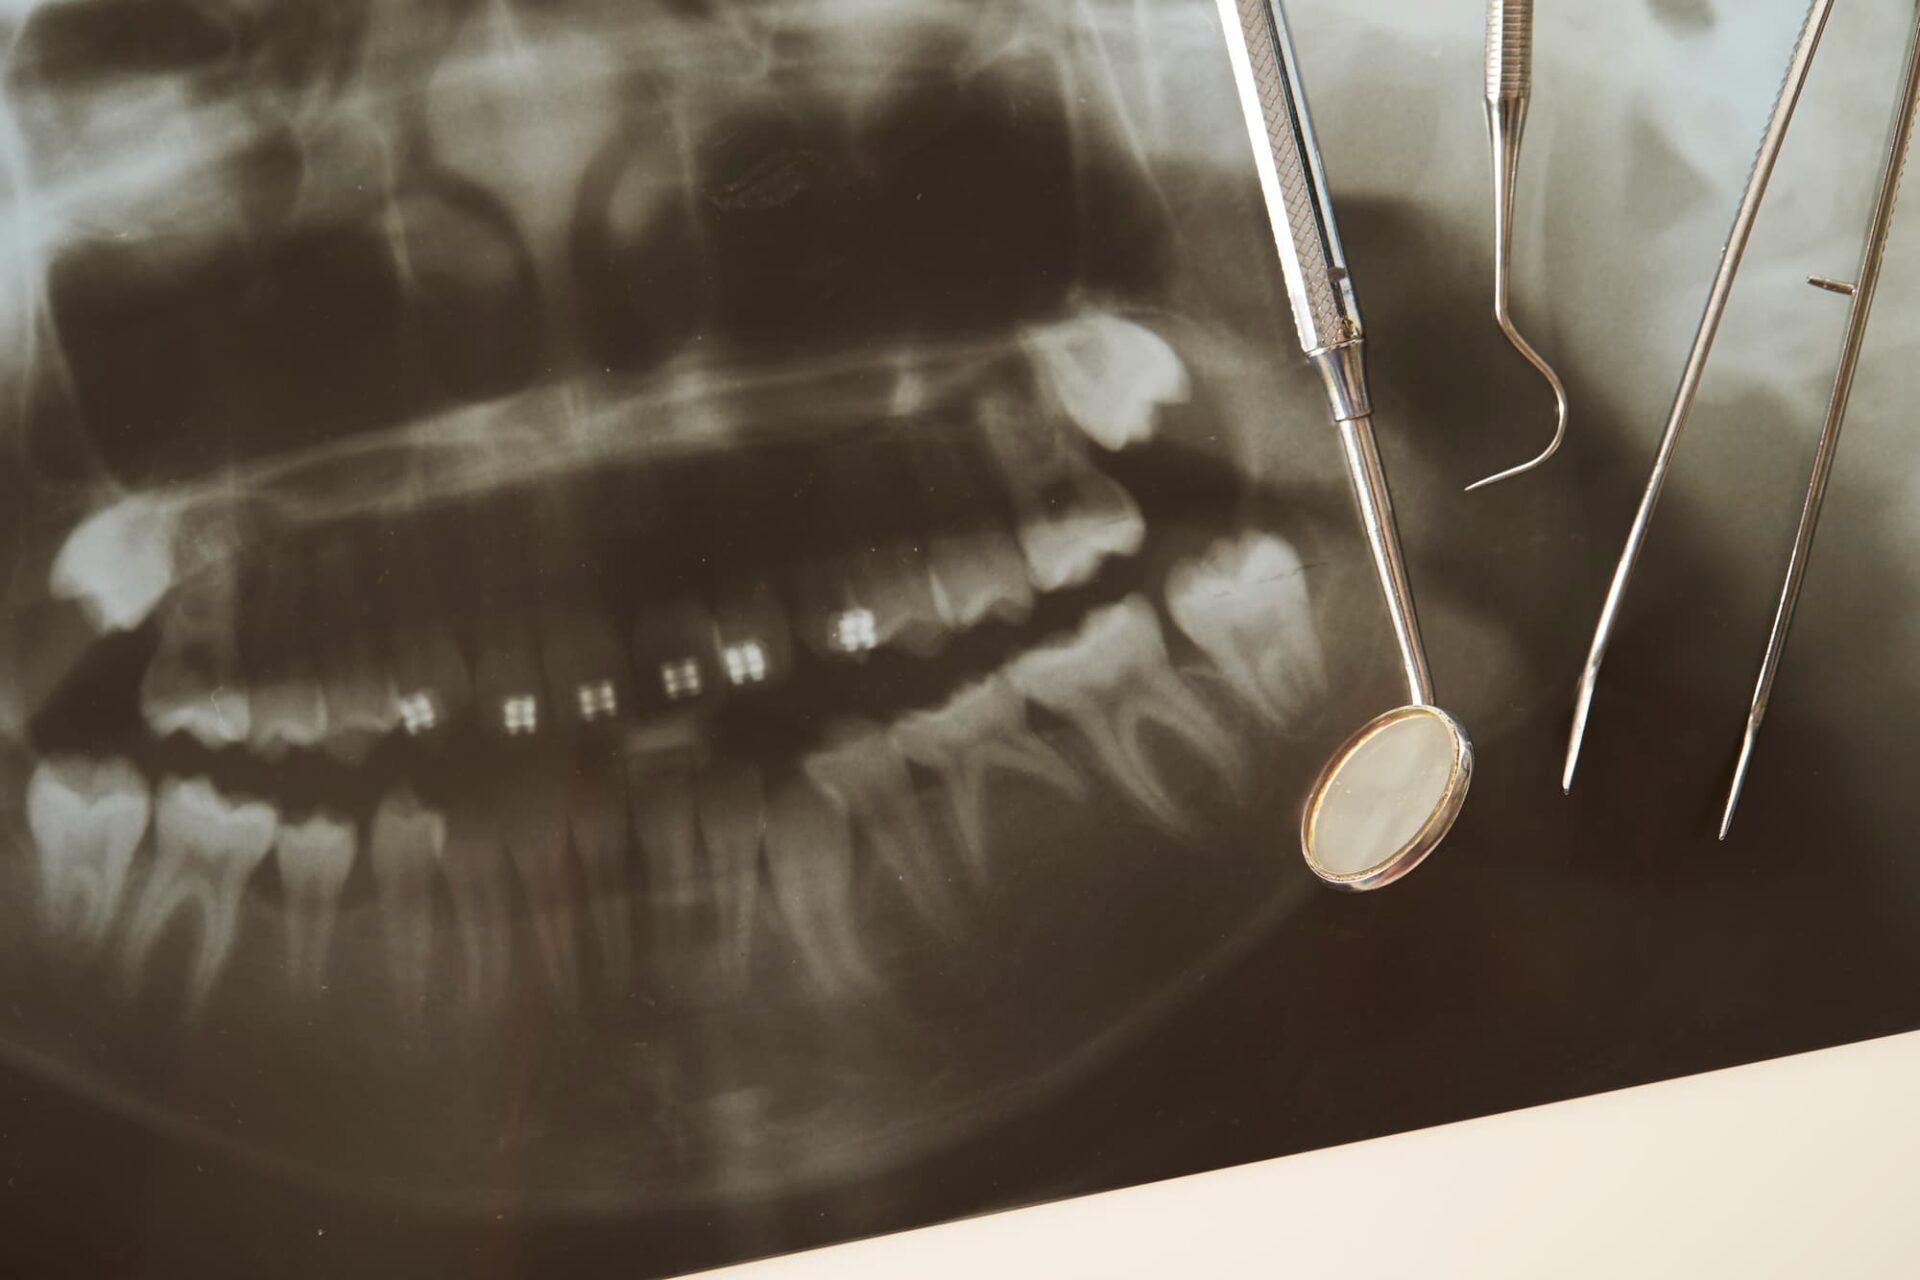

治療の前には、銀歯や周囲の歯の状態を確認します。まずは目視で、銀歯と天然歯の境界部分や表面に汚れ、変色、隙間、摩耗、破損がないかを丁寧に確認します。次に、レントゲン撮影を行い、銀歯の下に虫歯や骨の吸収があるかどうかを確認します。

さらに、銀歯や周辺の歯を軽くたたいて、痛みの有無や違和感を確認することもあります。加えて、銀歯や隣接する歯を手や器具で軽く押して、動揺がないか確認する触診も行います。

こういった検査によって虫歯の原因を探り、適切な治療法を考えます。